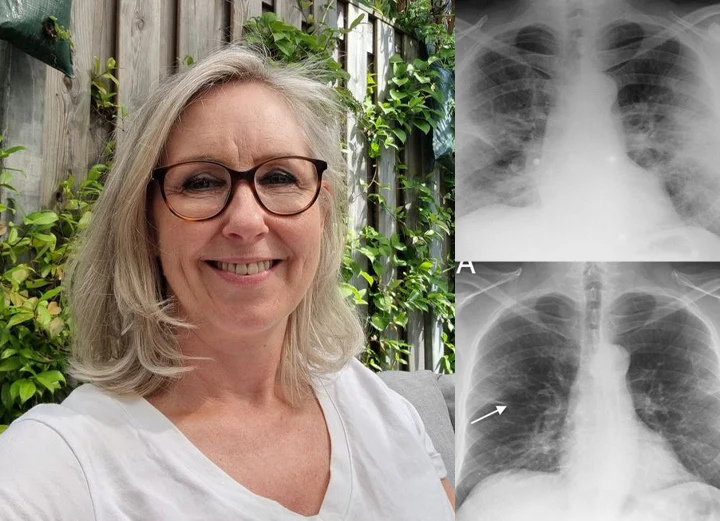

Hear From 150,000+ Satisfied Customers Who Cleared Their Lungs with Timilk® HerbaAir

“Living in a polluted city, I battled constant wheezing and exhaustion for years. Medications helped but made me feel drained. With Timilk® HerbaAir nasal inhalation, I felt my airways open up within 2 minutes of first use! My cough disappeared within two weeks, and breathing became much smoother. The instant relief is incredible.” — Linda M., Age 52,

“After smoking for over a decade, climbing stairs left me breathless. I tried various remedies with no improvement until Timilk® HerbaAir nasal inhalation. I couldn’t believe how quickly I felt relief! After one week, I could walk up five floors without gasping. My constant cough vanished completely.” — Bianca F., Age 47,

“With emphysema for ten years, every morning was a struggle with tight chest and constant mucus. Mullein teas helped a little, but Timilk® HerbaAir nasal inhalation gave me immediate soothing relief from the very first use. Within two weeks, I could walk my dog again without stopping.” — Karen S., Age 68,

Over 465,000+ Nigerians & World-wide Users Have Already Transformed Their Lungs Health

Miss Michael Grace

“I used to have chest congestion and difficulty breathing, but after using HerbaAir Mullein Lung Purifier, my chest feels clearer and breathing is much easier. I feel healthier and more comfortable now. I truly recommend it.”